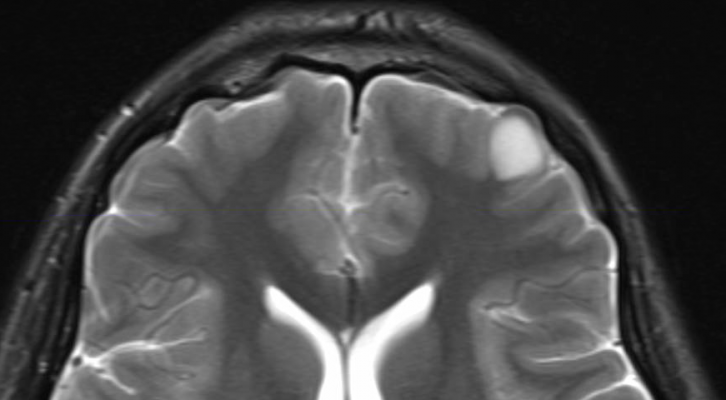

Dec. 3, 2012 – In the management of gliomas — or tumors that originate in the brain — precise assessment of tumor grade and the proliferative activity of cells plays a major role in determining the most appropriate treatment and predicting overall survival. Research published in the December issue of The Journal of Nuclear Medicine (JNM) highlights the potential of imaging with 3'-deoxy-3'-F-18-fluorothymidine (F-18-FLT) positron emission tomography (PET) to noninvasively and accurately provide tumor-specific details to guide management of patients with gliomas.

In the study led by Yamamoto, researchers retrospectively evaluated F-18-FLT uptake in patients with newly diagnosed (36 patients) and recurrent (20 patients) gliomas. Patients underwent F-18-FLT PET scans; tissue specimens were then taken to obtain a pathological diagnosis. The F-18-FLT images were analyzed by two nuclear medicine physicians, who identified tumor lesions as areas of focally increased uptake exceeding that of normal brain background, and who determined the tumor-to-normal (T/N) ratio. Results the 18-F-FLT PET scan were compared with tumor grade and proliferative activity estimated from the tissue specimens.

Researchers found that there was significant difference in the T/N ratio among different grades of newly diagnosed and recurrent gliomas. F-18-FLT uptake correlated more strongly with the proliferative activity in newly diagnosed gliomas than in recurrent gliomas and provided a more comprehensive view to determine tumor grade as compared to a single tissue specimen.